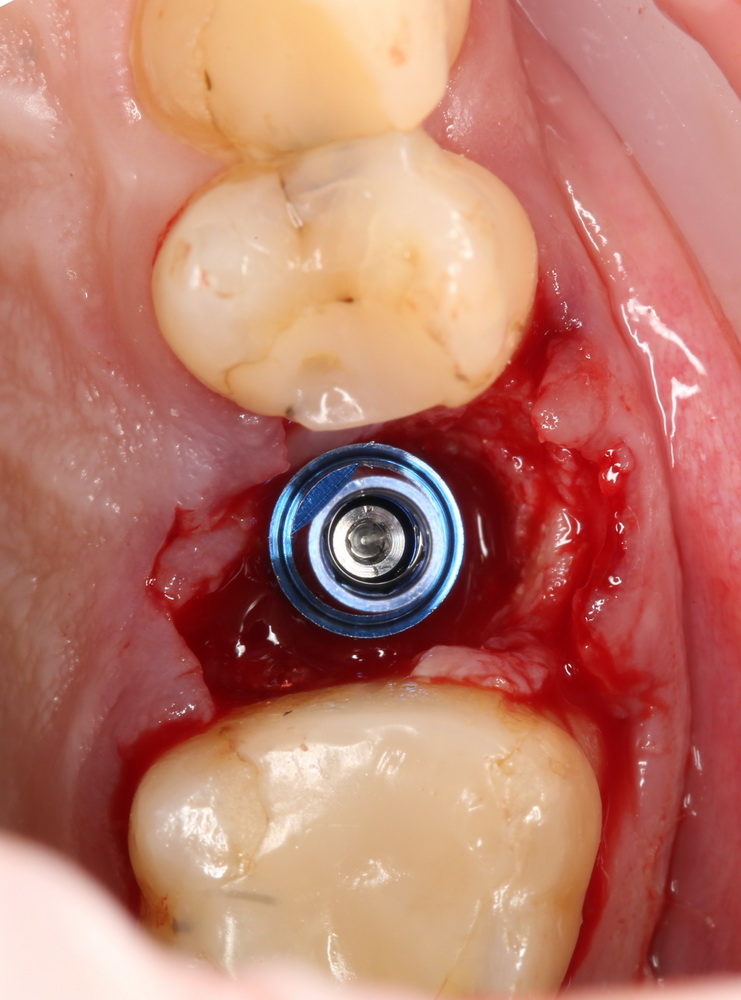

Затем лунка зуба адаптируется, в нее устанавливается имплантат, в данном случае Friadent XiVE диаметром 4.5 и длиной 13 мм:

Если не предполагается немедленная нагрузка (изготовление коронки на имплантат), первичная стабильность не является обязательной. Тем более, нельзя пытаться ее достичь, меняя положение и, особенно, погружение импланта. Если есть опасения, можно закрыть имплантат заглушкой, а саму лунку герметично ушить, используя свободный слизистотканный аутотрансплантат или (что разумнее) коллагеновую матрицу Mucograft Seal. Про последнюю обязательно расскажу вам, как только наберу достаточное количество клинических примеров.